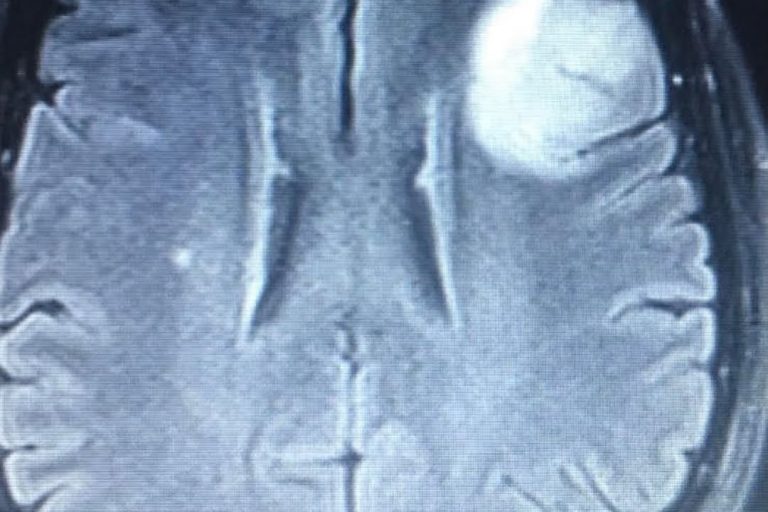

Meet Lin Sanders—a true inspiration of resilience and determination! Part 1 Lin underwent a complex two-level lumbar fusion at Texas Neuro-Spine Surgery. The procedure involved an anterior lumbar interbody fusion (ALIF) at L3-4 and L4-5, followed by laminectomies and pedicle screw instrumentation at the same levels. These surgeries were performed to help address her back…